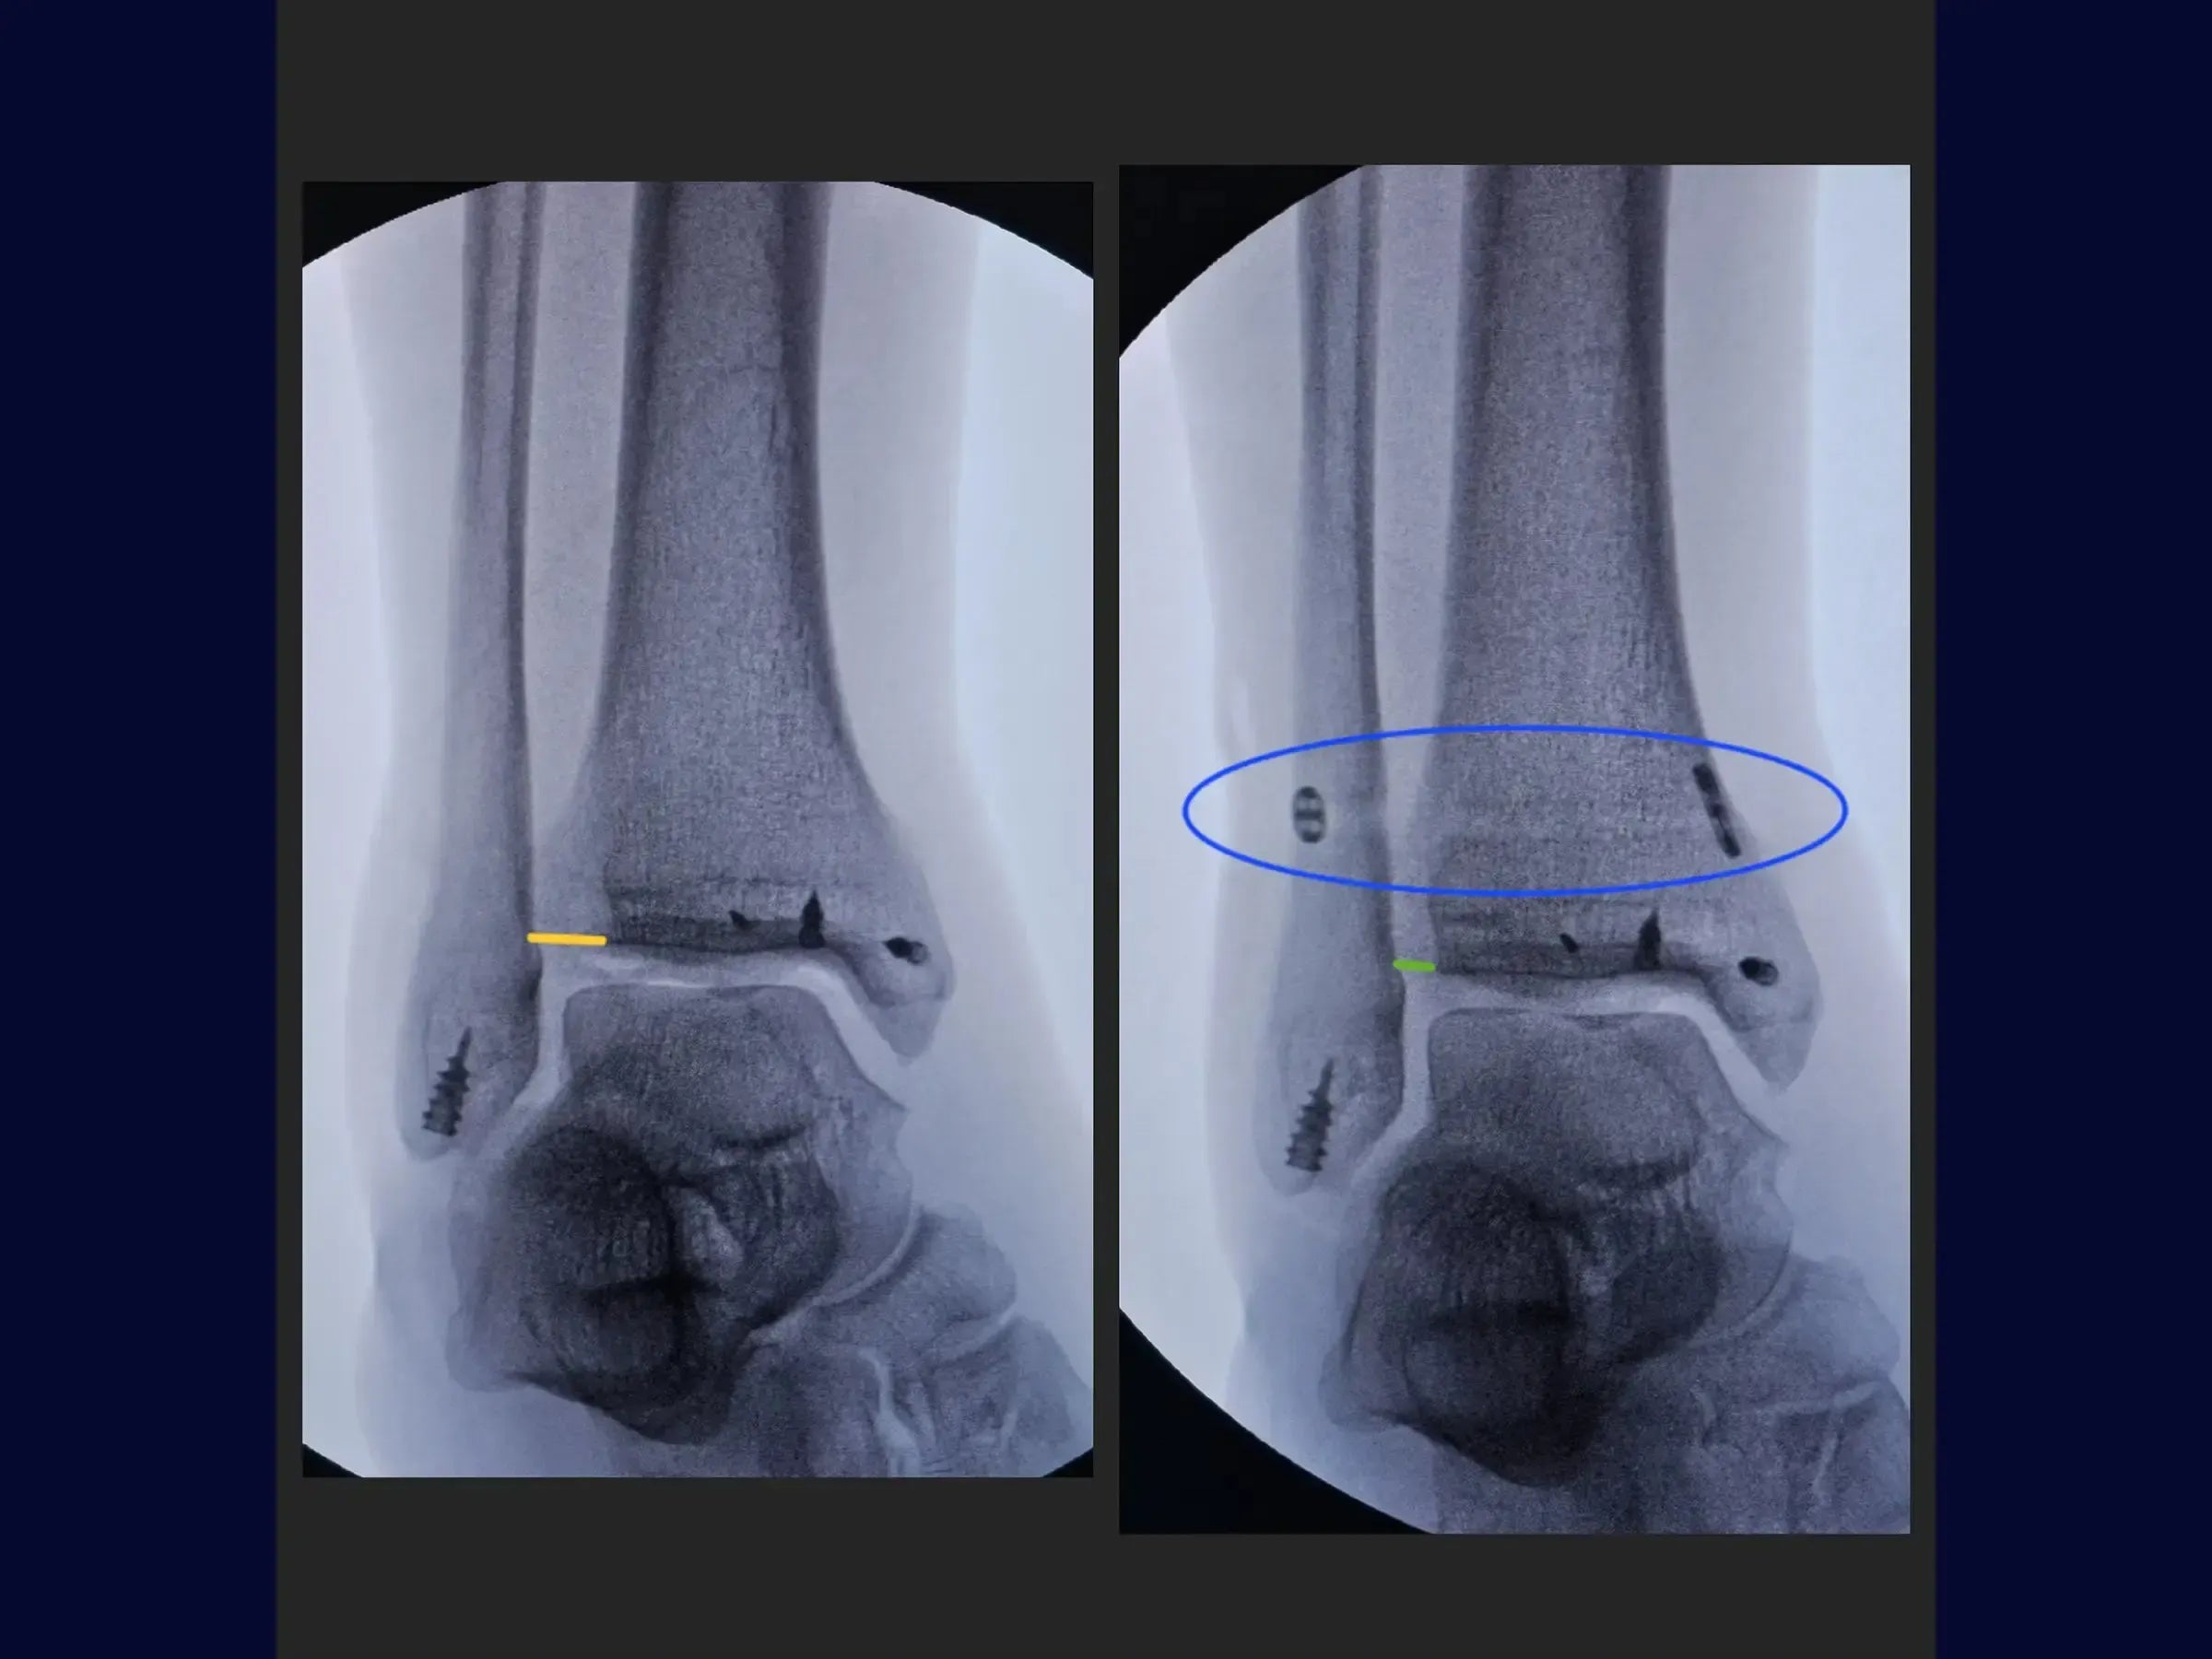

- Reconstrucción detallada del ligamento (deltoides y sindesmosis): técnicas de reinserción de las porciones anterior y posterior del ligamento deltoides con anclajes y estabilización de la sindesmosis con un dispositivo de fijación.